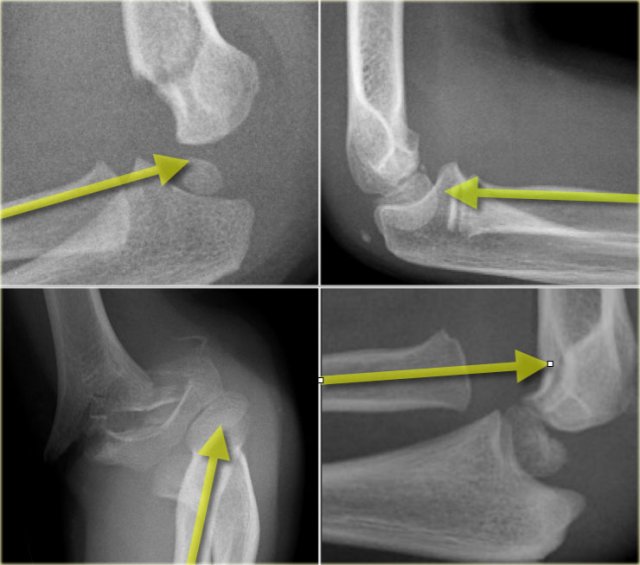

There are two important lines which help in the diagnosis of dislocation and fracture .

These are the Radiocapitellar line and the Anterior humeral line.

Radiocapitellar line

A line drawn through the centre of the radial neck should pass throught the centre of the capitellum, whatever the positioning of the patient, since the radius articulates with the capitellum (figure).

In dislocation of the radius this line will not pass through the centre of the capitellum.

On the left we see, that the radiocapitellar line goes through centre of the capitellum on every radiogragh even though C and D are not well positioned.

Notice supracondylar fracture in B.

On the left more examples of the radiocapitellar line.

The right lower image shows an obvious dislocation of the radius.